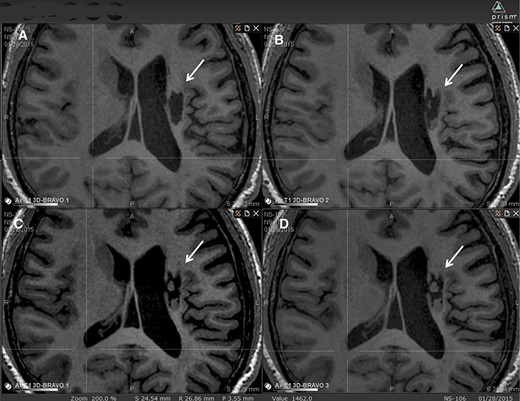

在6個月的隨訪中,所有9名受試者均觀察到新組織,源自腦軟化梗塞腔。該腔內(nèi)組織外觀具有以下特征:短期活力(術(shù)后第一次MRI與基線相比的組織外觀)—9例中有9例;生長(術(shù)后至少兩次MRI中新組織增加)—6例中有6例;穩(wěn)定(術(shù)后至少兩次MRI中新組織無變化;即生長平臺期,最長為24個月)—6例中有5例;無法獲得24個月后的長期活力。圖2顯示了腔內(nèi)組織生長的縱向MRI示例。9名受試者的梗塞腔內(nèi)這種無關(guān)組織的存在都很明顯(圖3)。

圖中顯示了B組 (#106) 受試者在T1MRI上隨時間的變化。

(A):基線時,(B) 6個月隨訪時,(C) 12個月隨訪時,(D) 24個月隨訪時。箭頭表示梗塞腔。

可以看到兩個組織團塊,在基線時不存在,推測是來自植入的NSI-566,隨著時間的推移,它們似乎慢慢填滿了腔體。